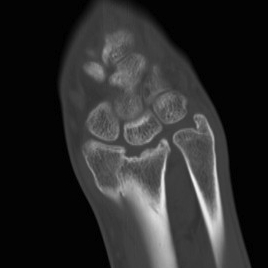

CT

malunionmalunionmalunion